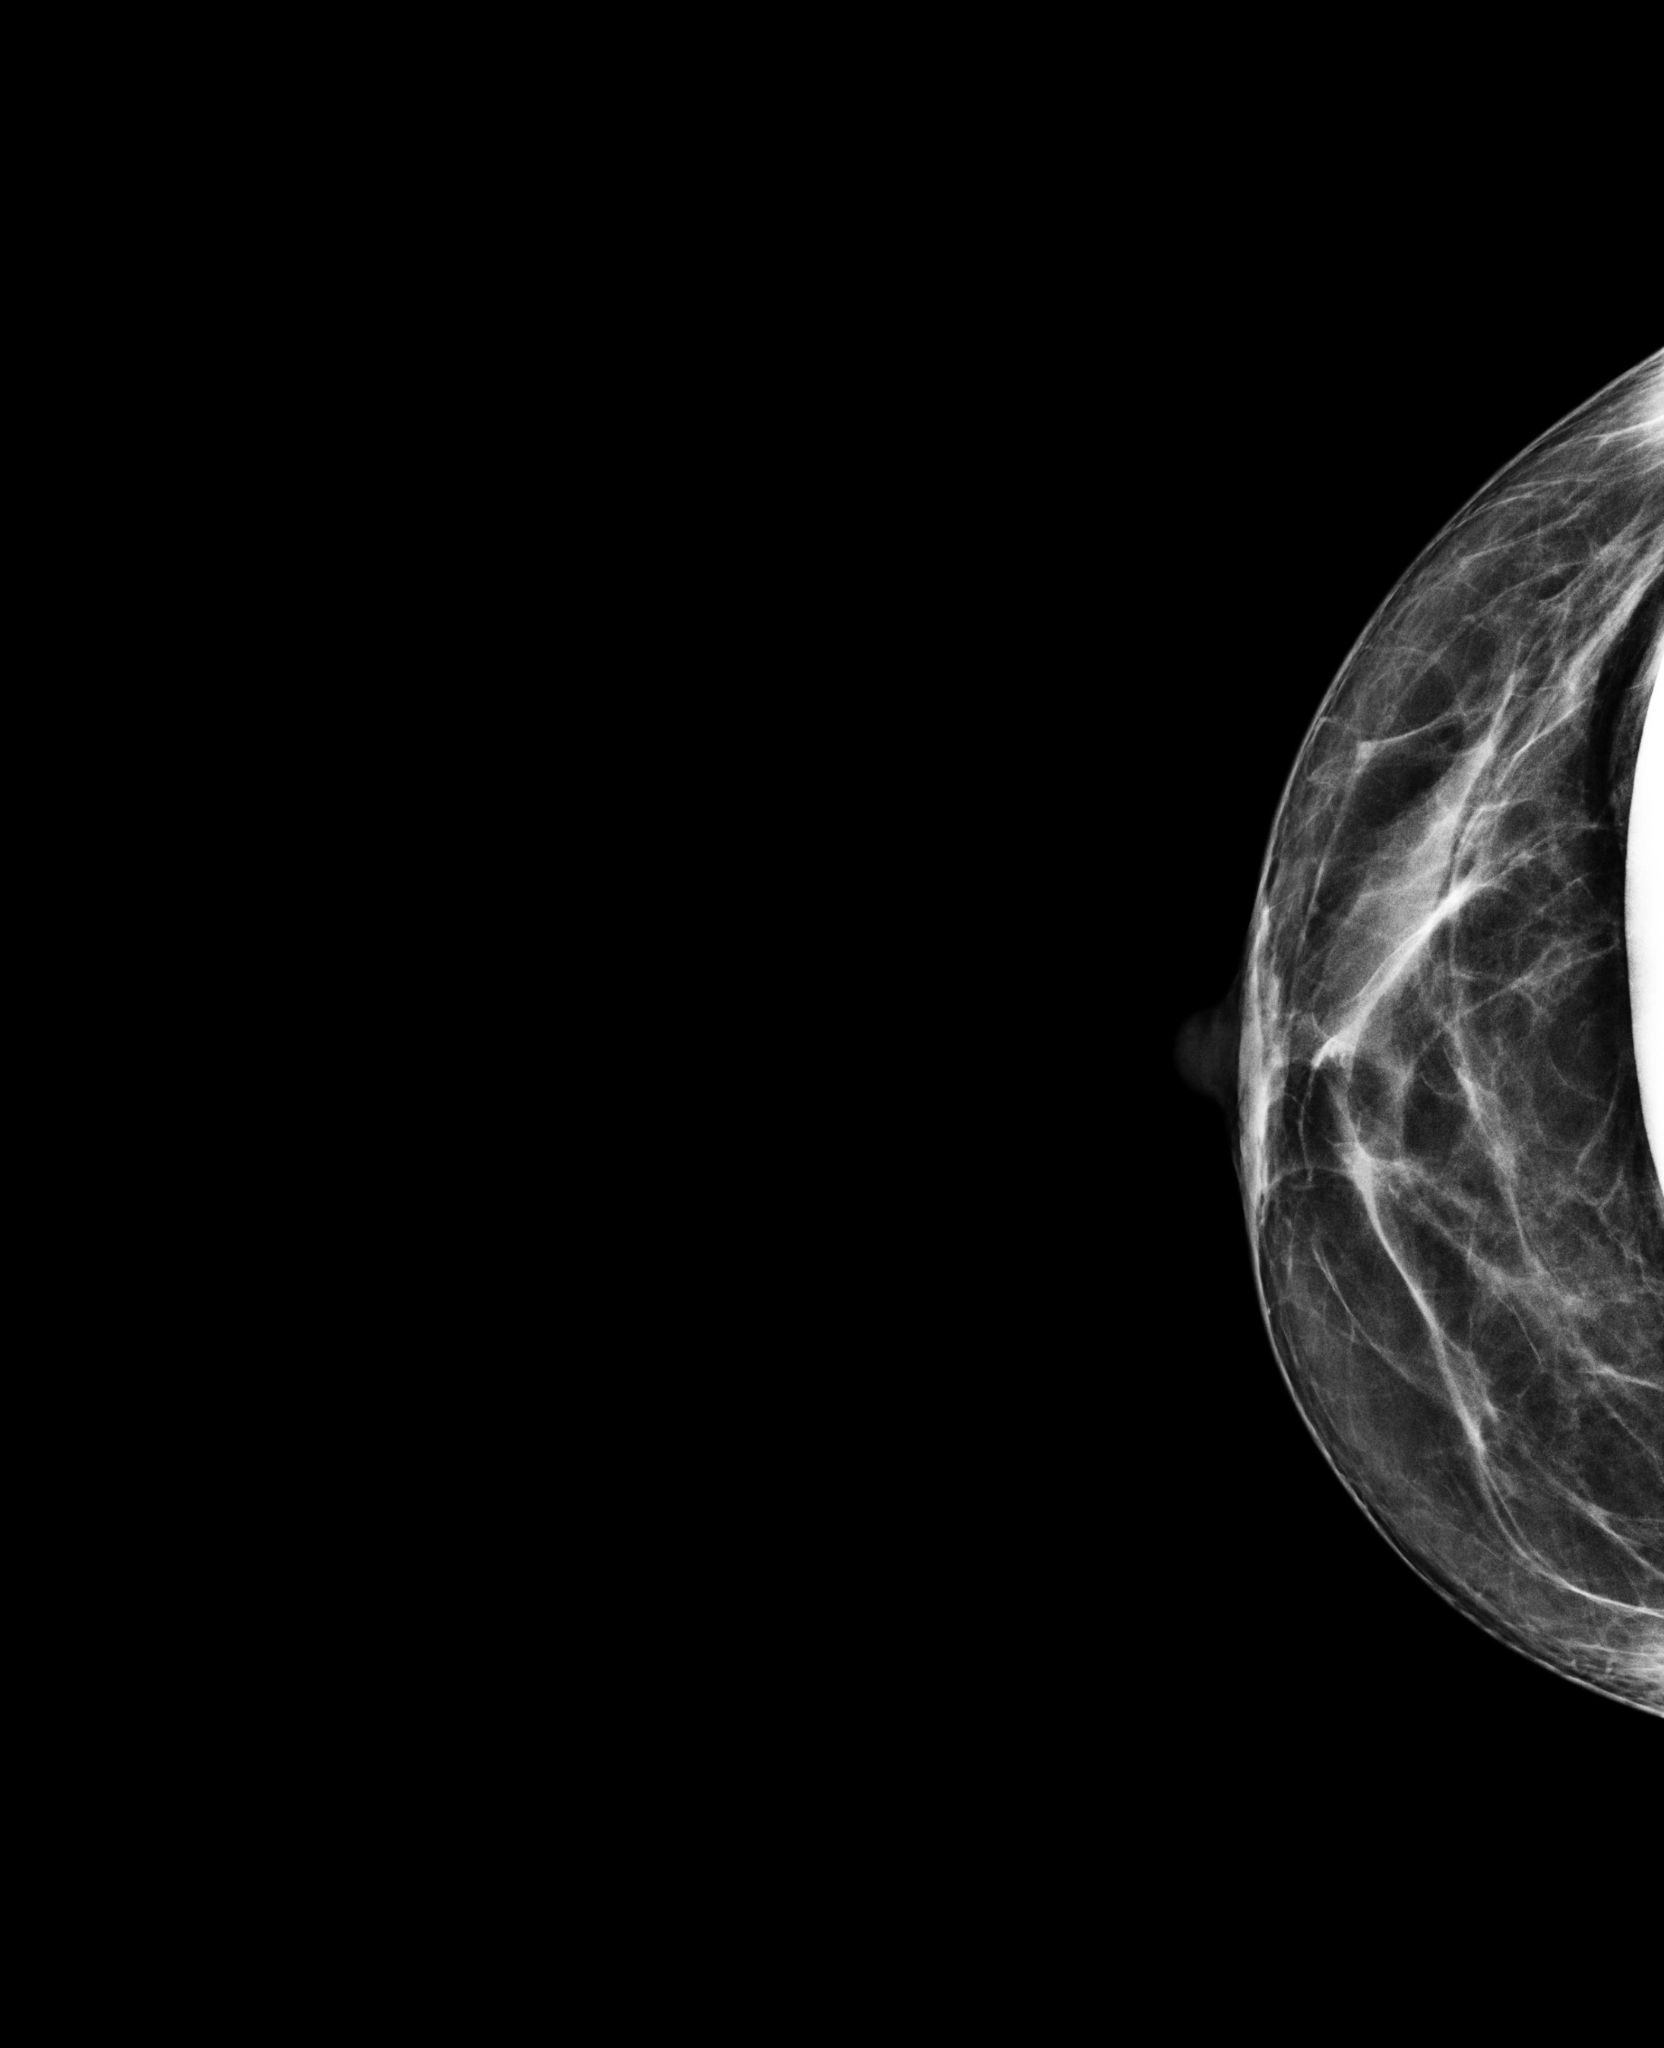

BreastScreen NSW radiographers are trained in taking mammograms for women with breast implants. The pictures below show how special techniques are used to image the breast tissue around implants.